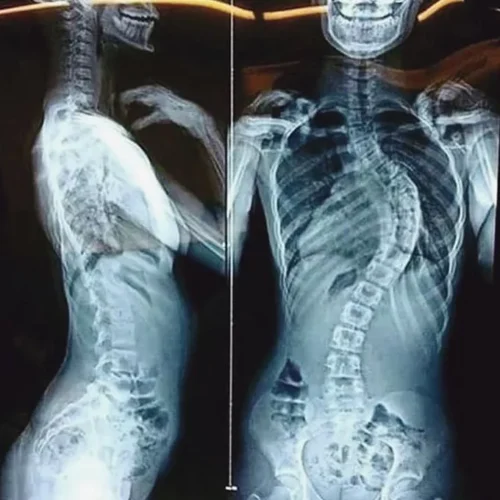

اعوجاج العمود الفقري هو انحناء غير طبيعي في العمود الفقري يجعل الظهر يبدو مائلًا إلى أحد الجانبين. وقد يكون الانحناء بسيطًا وغير ملاحظ، أو شديدًا ومؤثرًا على وظيفة الرئتين والقلب. يُصنَّف إلى أنواع عدة:

نعم، تشير الدراسات الحديثة إلى أن الانحناء الشديد في الجزء العلوي من العمود الفقري، خصوصًا في الحالات التي تتجاوز فيها زاوية الاعوجاج 70-80 درجة (زاوية كوب)، قد يسبب ضغطًا على القلب والرئتين. هذا الضغط الميكانيكي يمكن أن يعيق وظائف القلب ويؤدي إلى مضاعفات خطيرة مع مرور الوقت.

تضييق المساحة داخل القفص الصدري: مما يضغط على القلب ويقلل من قدرته على التمدد والانقباض بشكل طبيعي.